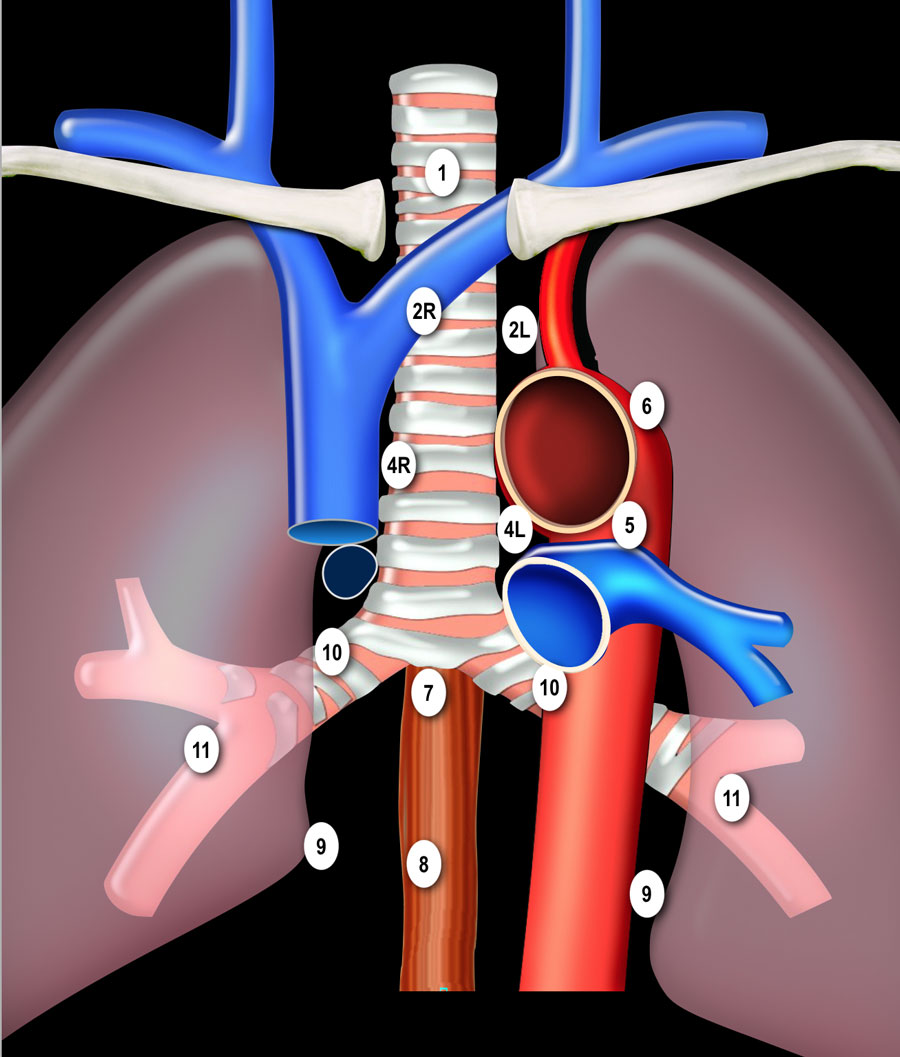

N-стадирование Классификация регионарных лимфатических узлов IASLC 2009 г.

Граница между лимфатическими узлами 10 и 4 группы находится на правой нижней границе непарной вены и на левой верхней границе легочной артерии (отличие N1 и N2 стадий). Достаточно важно разделять лимфатические узлы 1-ой группы и 2/3-ей групп

(отличие N3 и N2 стадий). Граница между группами лимфатических 4R и 4L является левый латеральный контур трахеи, а не срединная линия. Паракардиальные, лимфатические узлы молочных желез, диафрагмальные,

межреберные и подмышечные лимфатические узлы не входят в карту

лимфатических узлов согласно IALSC, несмотря на то, что они редко, но

могут вовлекаться в патологический процесс. ПЭТ/КТ является методом выбора при определении N-статуса. |